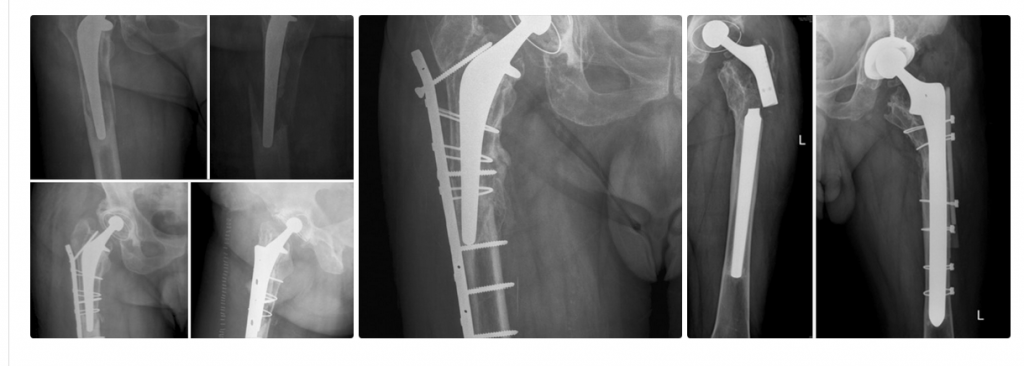

Il trattamento chirurgico risulta frequentemente complicato dallo scarso bone stock femorale prossimale o dalle condizioni di salute generale scadenti del paziente. Mentre nei casi classificati B1 secondo Vancouver una sintesi può risultare più semplice ed efficace, la revisione è necessaria se l’osso è di scarsa qualità o in caso di mobilizzazione dell’impianto.

Gli studi selezionati mostrano che l’incidenza di fratture periprotesiche di femore risulta variabile e si aggira intorno a un valore medio del 4%, maggiore nei pazienti con stelo non cementato o in caso di precedenti revisioni di protesi d’anca.

Numerosi autori sono concordi nel definire l’osteosintesi il trattamento ottimale per le fratture di tipo B1, la revisione quello ottimale per le B2, B3 e C; non è raro trovare casi

di B2 trattate con successo tramite open Reduction Internal Fixation (ORIF) e, viceversa, B1 fallite nonostante la corretta indicazione chirurgica.

Classificare le fratture ha permesso di semplificare le scelte operatorie; tra le classificazioni esistenti (es. Johansonn,1981; Beals e Tower, 1996) quella di Vancouver è la più utilizzata: include la sede di frattura, la stabilità dello stelo protesico e il bone stock femorale prossimale. Le fratture da B1 a C secondo Vancouver necessitano nella maggior parte dei casi di un intervento chirurgico che può variare dalla sintesi in caso di B1 alla revisione protesica dello stelo in caso di B2,

B3eC, ma il confine non è sempre così ben delineato. Sia secondo la letteratura, sia analizzando la nostra casistica risulta evidente che entrino in gioco numerosi altri fattori: ad esempio, uno stelo che appare mobilizzato alle indagini radiografiche preoperatorie (Rx e, eventualmente, TC) può

risultare stabile a sufficienza in sala, dirottando la decisione chirurgica verso una sintesi. Le condizioni cliniche generali scadenti (età, eventuali patologie cardiovascolari, demenza senile, deambulazione scarsa o nulla, patologie neurologiche associate, esiti di traumi, aumentato rischio settico) e la scarsa compliance dei pazienti spingono il chirurgo a eseguire l’intervento meno invasivo possibile. Viceversa la relativamente giovane età, le buone condizioni cliniche generali e un buon bone stock complessivo permettono una revisione di stelo, nei casi in cui è indicata, con minor probabilità di complicazioni. Infine, non sono rari i casi di fallimento della sintesi pur in caso di fratture tipo B1.